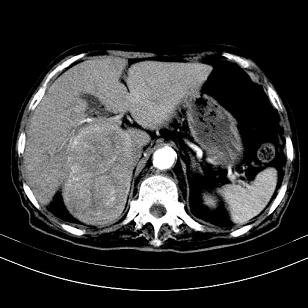

考虑右肝后叶肝癌(部分外生)伴肝内多发性转移;右侧肾上腺区恶性肿瘤并肝转移待排。

考虑右侧肾上腺肿瘤并肝内多发转移。右侧肾上腺呈“八”字形,包括内侧枝及外侧枝,内侧枝受压,考虑外侧枝原发肿瘤。”

考虑肝右后叶肝癌(部分外生)伴肝内多发性转移;不排除右侧肾上腺区恶性嗜铬细胞瘤并肝转移。